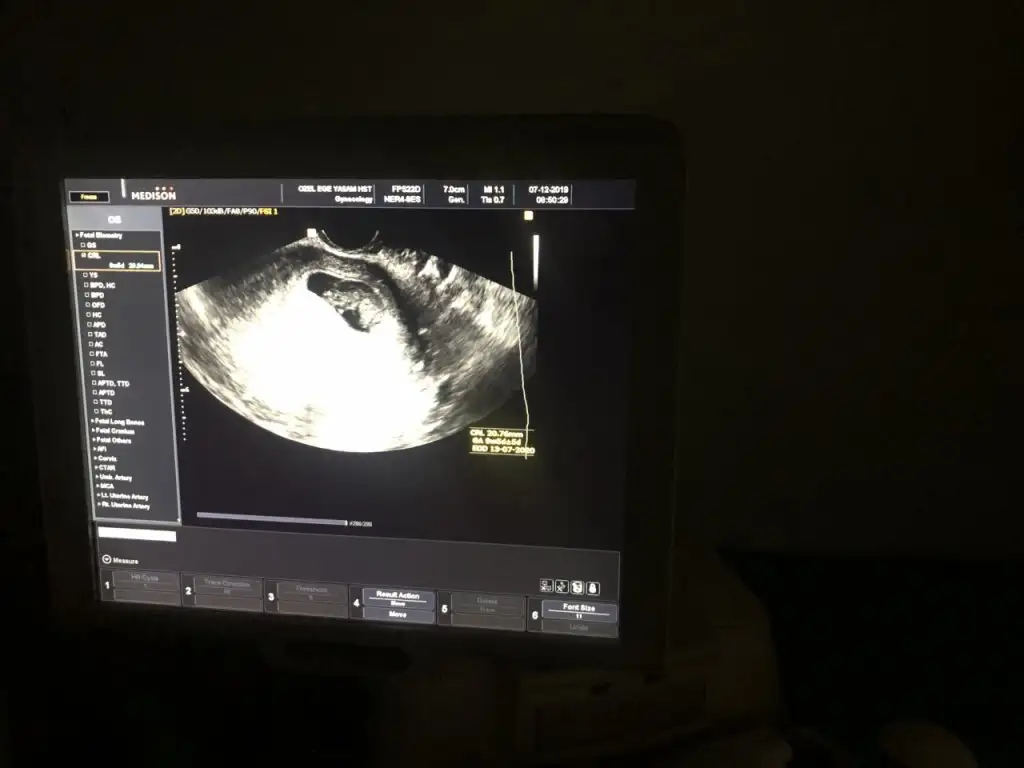

dr soylemeden siz gorun genital nub teorisi ( bebegin cinsiyeti)

Ikra meyra bide bu var